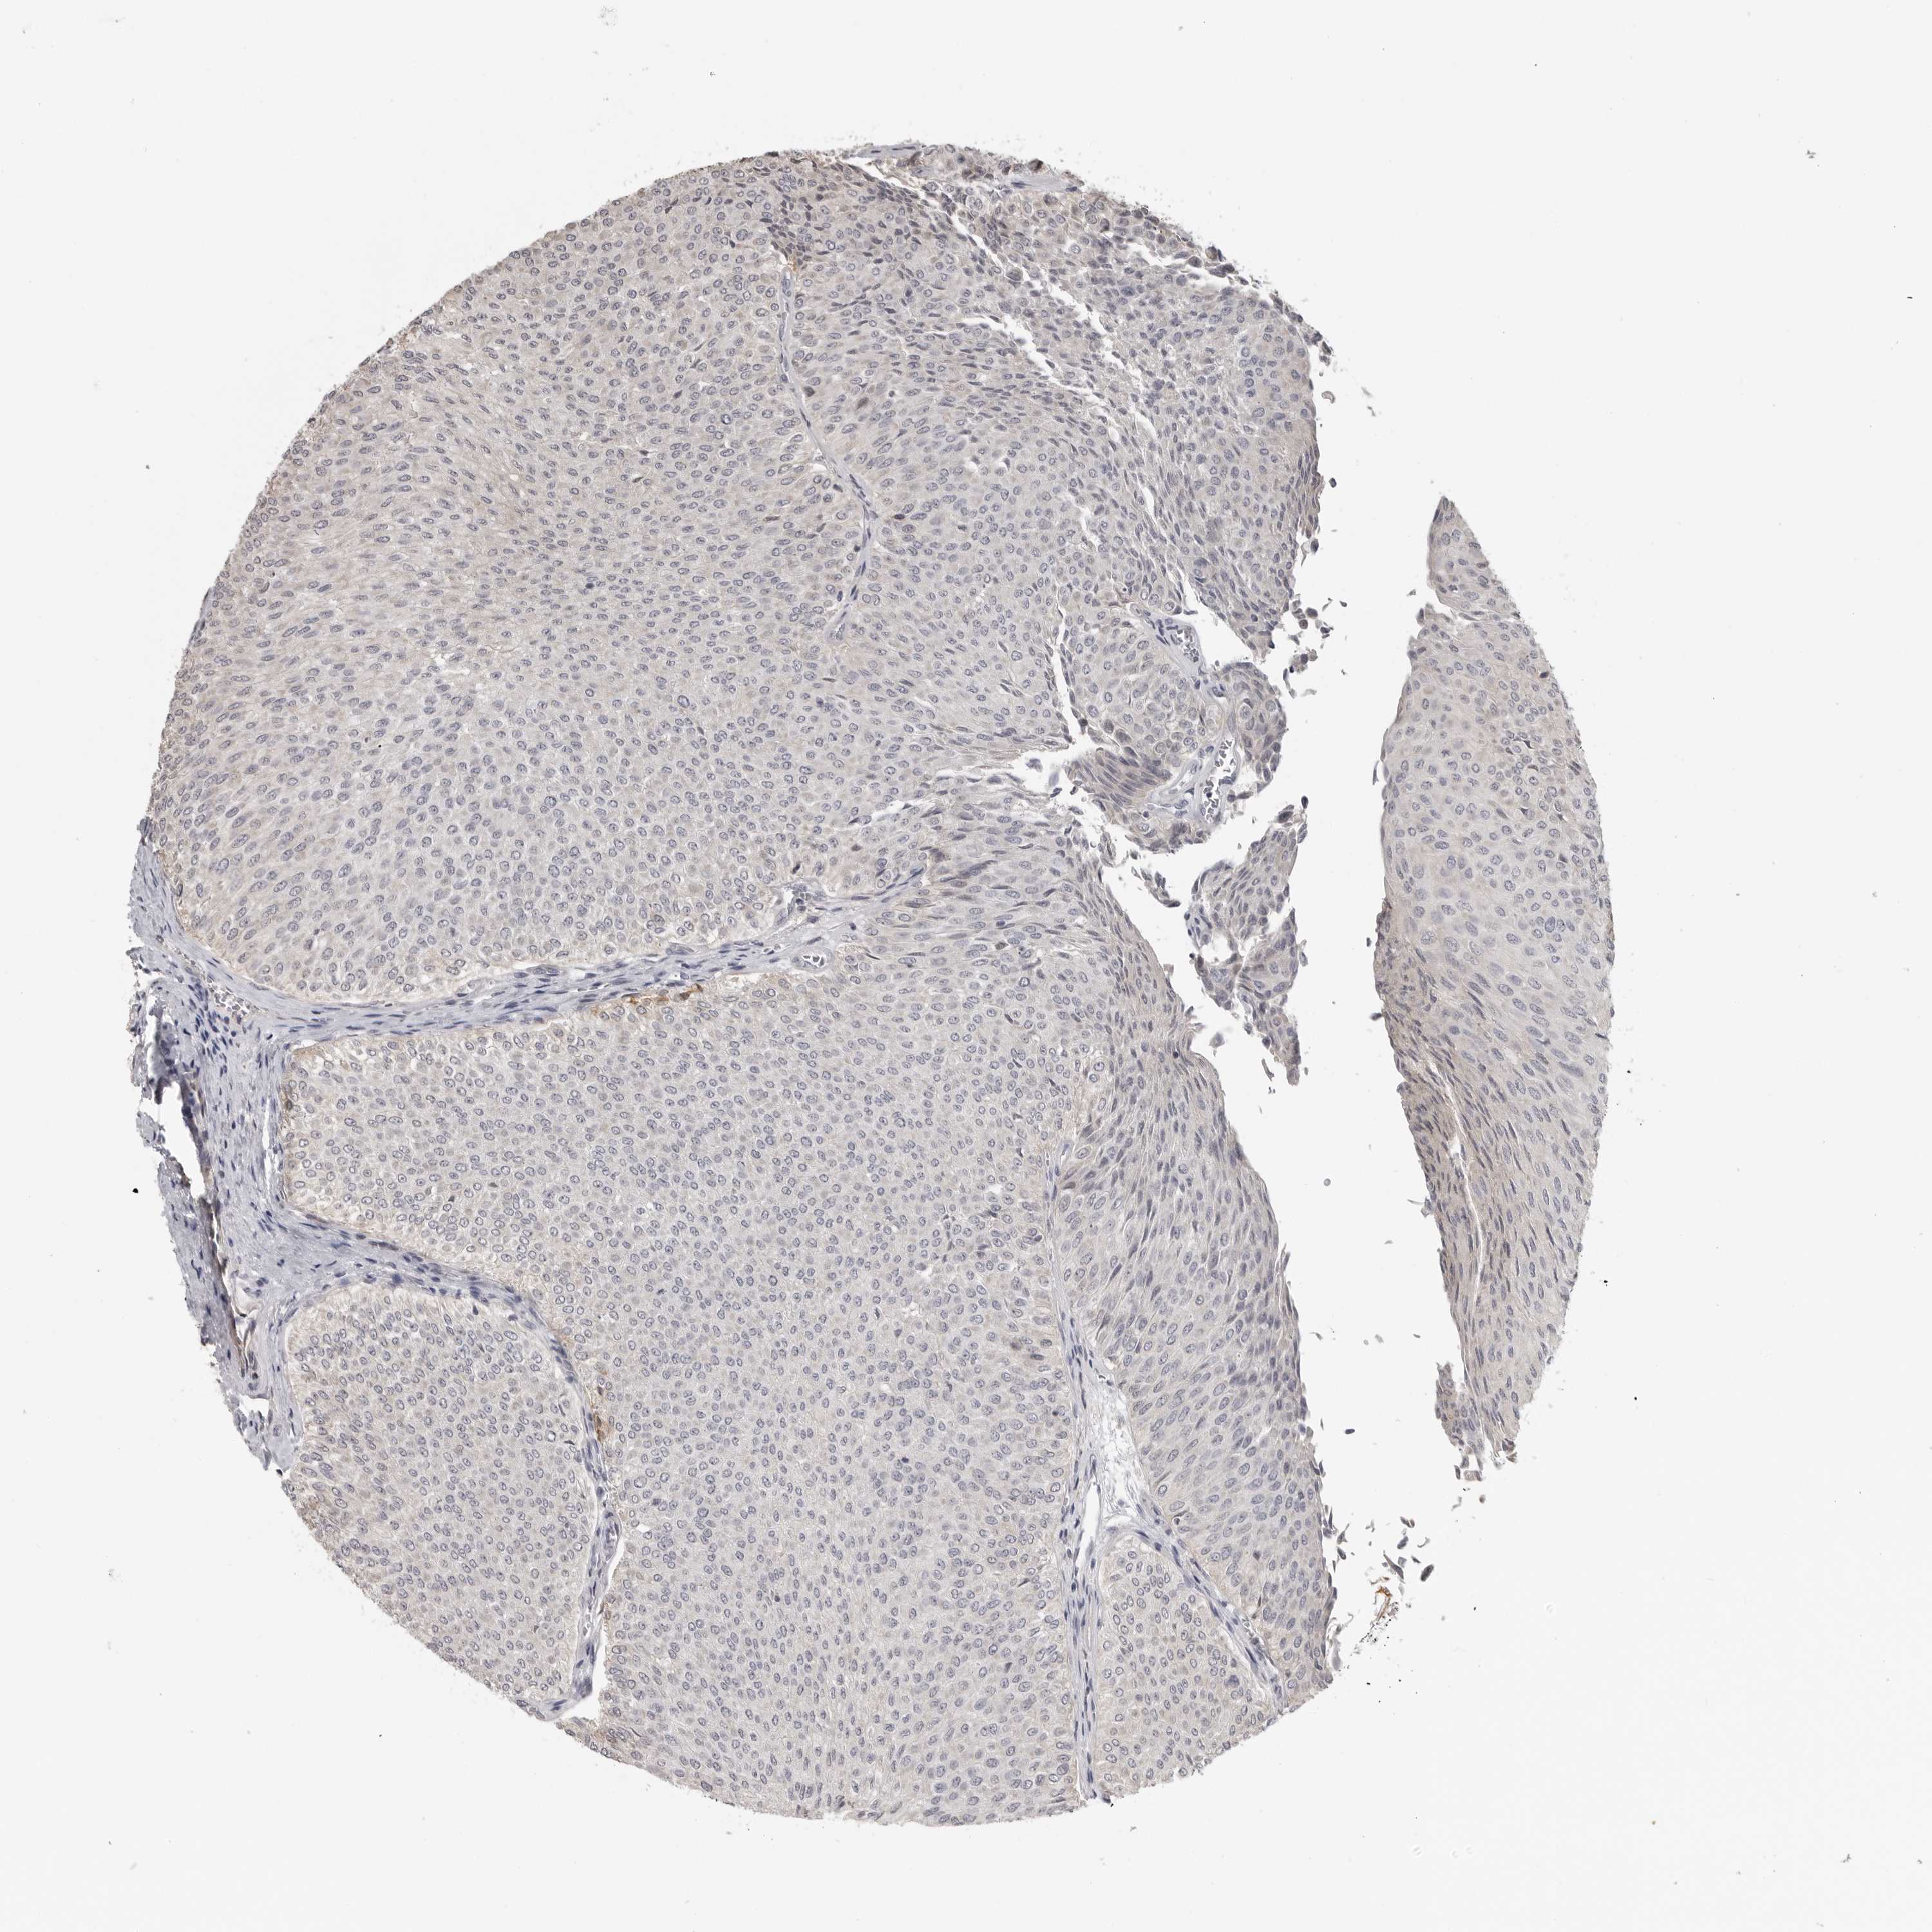

UROTHELIAL CANCER - Protein expressioni

A mouse-over function shows sample information and annotation data. Click on an image to view it in a full screen mode. Samples can be filtered based on level of antibody staining by selecting one or several of the following categories: high, medium, low and not detected. The assay and annotation is described here.

Note that samples used for immunohistochemistry by the Human Protein Atlas do not correspond to samples in the TCGA dataset.

Antibody stainingi

Antibody staining in the annotated cell types in the current human tissue is reported as not detected, low, medium, or high, based on conventional immunohistochemistry profiling in selected tissues. This score is based on the combination of the staining intensity and fraction of stained cells.

Each image is clickable and will lead to virtual microscopy that enables deeper exploration of all samples and also displays staining intensity scores, fraction scores and subcellular localization as well as patient and tissue information for each sample.

Antibody HPA027772

Urothelial carcinoma, Low grade

Urothelial carcinoma, High grade